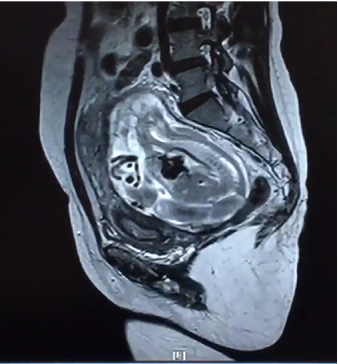

2月24日,我院产科、泌尿外科、麻醉手术科、胃肠外科、输血科等多学科合作成功救治一名腹腔妊娠特殊患者。这是我院多学科合作战胜疑难杂症的又一成功案例。近年来,作为三级甲等综合av线上 ,昆医大附二院始终坚持以患者为中心,充分发挥综合av线上 的优势,积极探索研究,持续加强学科建设,不断拓展多学科合作的广度和深度,利用多学科合作为人民群众解决了很多疑难杂症,用实际行动巩固脱贫攻坚成果,助力乡村振兴,为维护人民群众的健康持续奋斗。